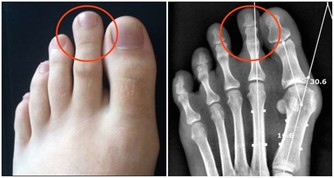

8、排出尿酸,改善痛風,嘌呤偏高時就是關節受罪時;